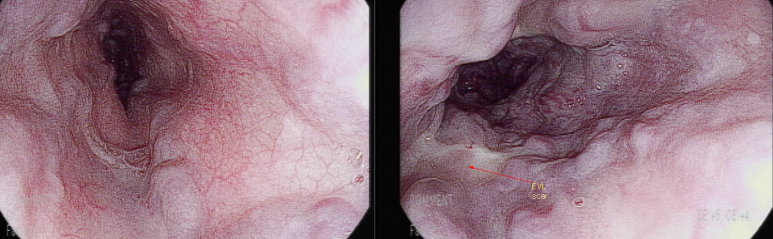

2년전 검진 위내시경; LsF3CbRCS(+++) 소견의 식도정맥류, 이전에 결찰술(EVL) 자국이 관찰되나

하부식도에 whale sign등 위험 소견을 동반한 모습